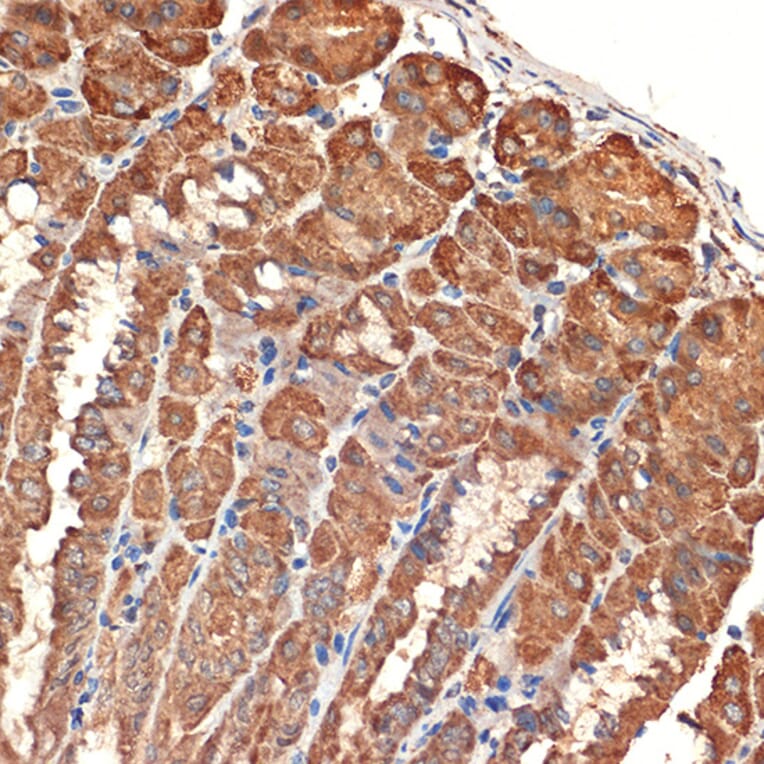

Immunohistochemistry analysis of paraffin-embedded mouse stomach using Anti-Bcl G/BCL2L14 Antibody [ARC2474] (A307106) at a dilution of 1:100 (40x lens). Perform microwave antigen retrieval with 10 mM Tris/EDTA buffer pH 9.0 before commencing with IHC staining protocol.